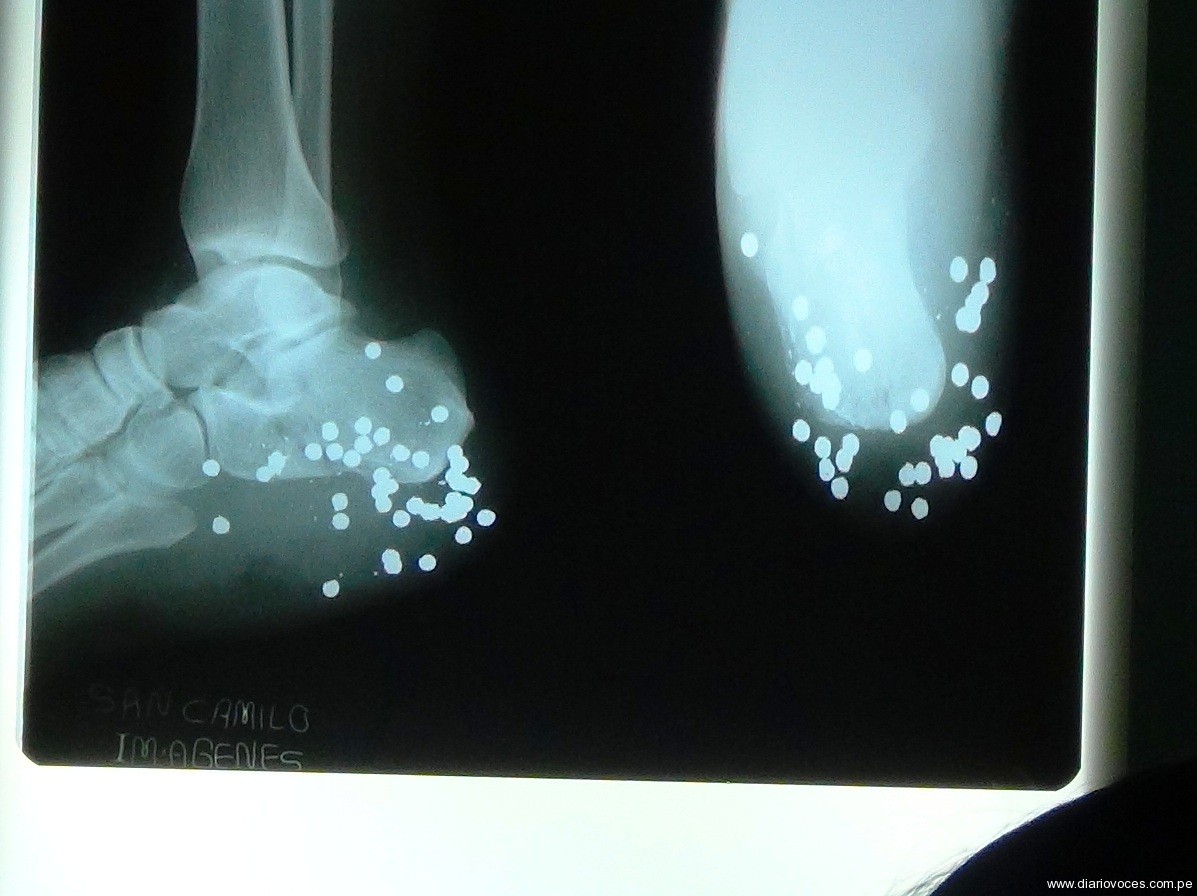

Agricultor vivió casi un mes con más de 50 perdigones en el pie

Un padre de familia vivió más de 25 días con cerca de cincuenta  perdigones en el pie derecho, tras caer accidentalmente en un trampero que fue colocado en un camino de herradura a tres horas de camino de Saposoa, ayer por la mañana ante el llamado de urgencia de sus familiares recibió apoyo de Manos Unidas y de la clínica San Camilo, para recibir atención médica.

Tras ser chequeado por el médico José Luis García Villaverde, determinaron internarlo de emergencia porque la herida presenta una infección avanzada, ayer por la tarde fue operado y le retiraron los perdigones que tenía alojado en el pie.

García Villaverde, manifestó que por disposición de los propietarios de la clínica San Camilo, el paciente recibirá atención gratuita y si en tres días no recibía atención médica, Humberto Sajamí hubiese perdido el pie derecho. (Hugo Anteparra)